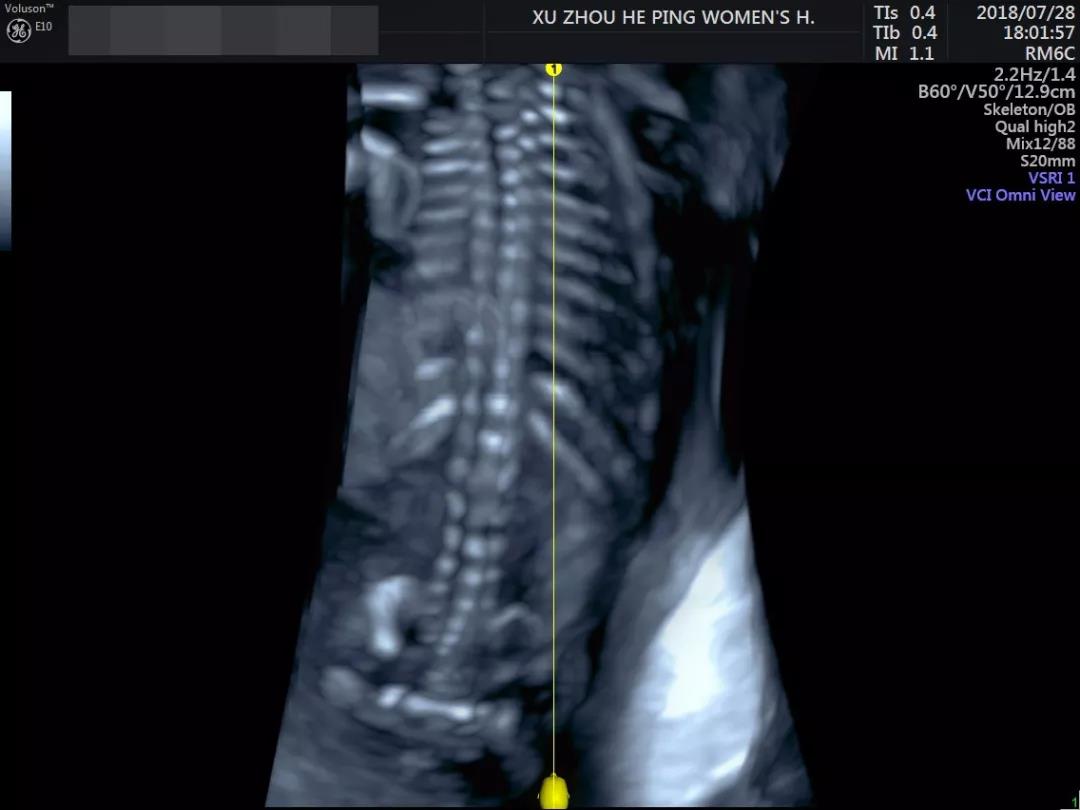

邱伟修博士操作和平GE-E10高清彩超设备

看到的宝宝身体都是这样▽

这样▽

不仅满足妈妈们一睹宝宝真容的要求

还可以清楚筛查宝宝的健康状况~